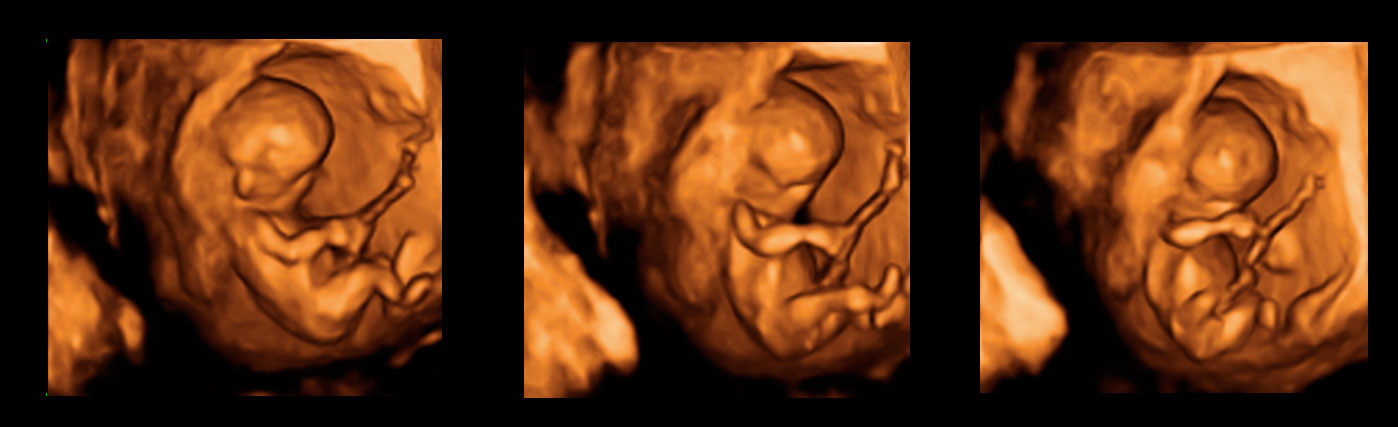

Imagen de trillizos de 13 semanas en ecografía 3D

En esta imagen en 3D muestra trillizos de 13 semanas. La ecografía nos informa de un hermano independiente, separado por una membrana de sus hermanos, que son gemelos. A su vez, los gemelos están separados, en bolsas independientes, por una membrana más fina. La gestación de trillizos es un embarazo de alto riesgo que ha de ser controlado muy de cerca por el ginecólogo.